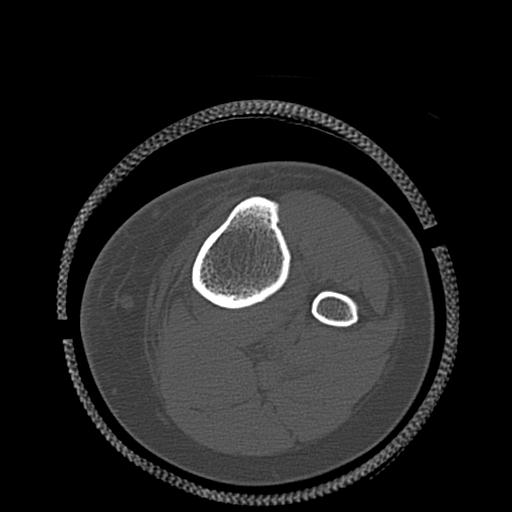

110286 2/17 股関節 2R 74歳女性 右人工骨頭

82084 1/14 1/20 股関節 2R 78歳男性 右人工骨頭

102811 1/13 股関節 2R 1/19 2R 80歳女性 右DHS